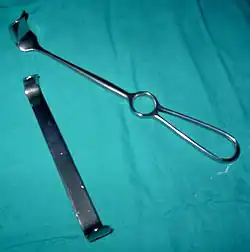

| Retractor |

|

Retractor | Handheld:

Self-retaining:

|